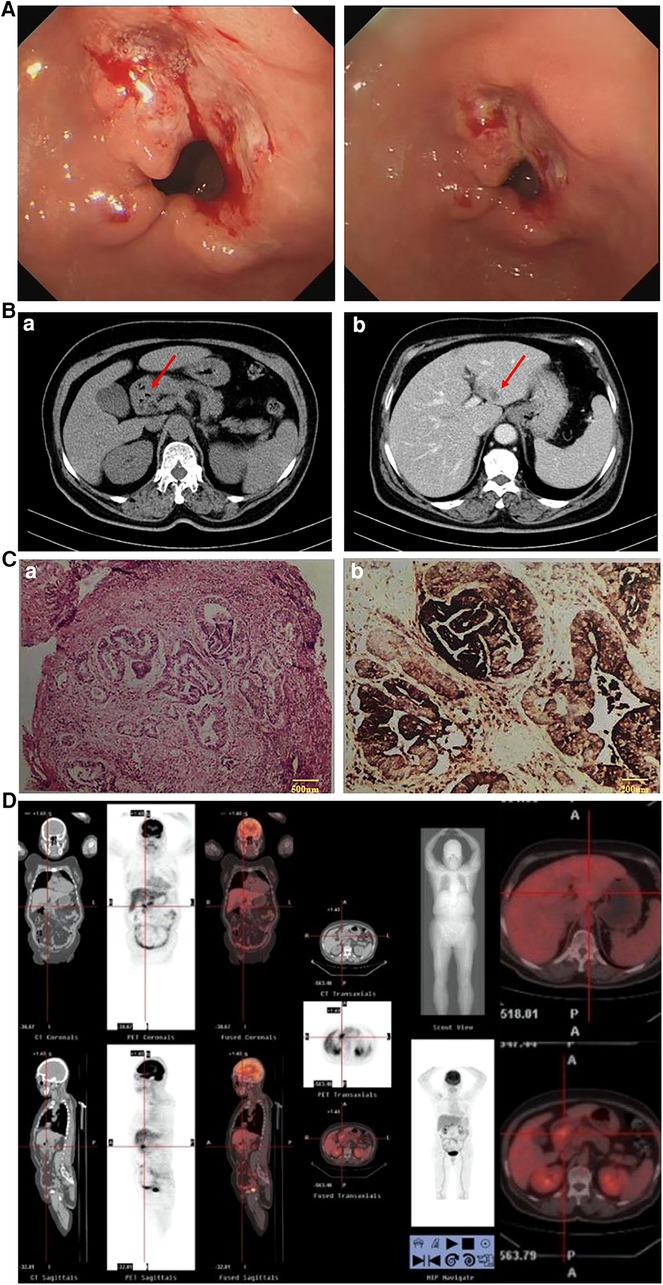

This was a case of a 66-year-old female patient with a complaint of abdominal discomfort for a month with no other associated symptoms. Physical examination revealed no pathological findings. Gastroscopy and computed tomography (CT) examinations revealed an irregular surface ulcer on the wall of the gastric antrum (Figure 1A) and a mass of 2.0 cm in diameter was found in the liver (Figure 1B). The pathological diagnosis from endoscopic biopsy was consistent with a moderately to poorly differentiated hepatoid adenocarcinoma (Figure 1C). PET-CT examination was then performed, and this showed that the stomach and liver masses were hypermetabolic (Figure 1D).

Figure 1. (A) Gastroscopy (April 1, 2020): gastric antrum ulcer. (B) CT (April 1, 2020): (a) Gastric antrum tumor; (b) Abnormal low density of left lateral lobe of the liver, considering metastasis. (C) Results of endoscopic biopsy: (a) HE staining; (b) AFP staining. (Gastric antrum) Moderately to poorly differentiated hepatoid adenocarcinoma. Immunopathology: AFP(+), HER-2(+), Ki-67(40%), PD-L1(22C3)(−), PD-1(−), CD4(+), CD8(+), MLH1(+), PMS2(+), MSH6(+), MSH2(+). (D) PET-CT examination: The masses of gastric antrum and left liver were hypermetabolic.